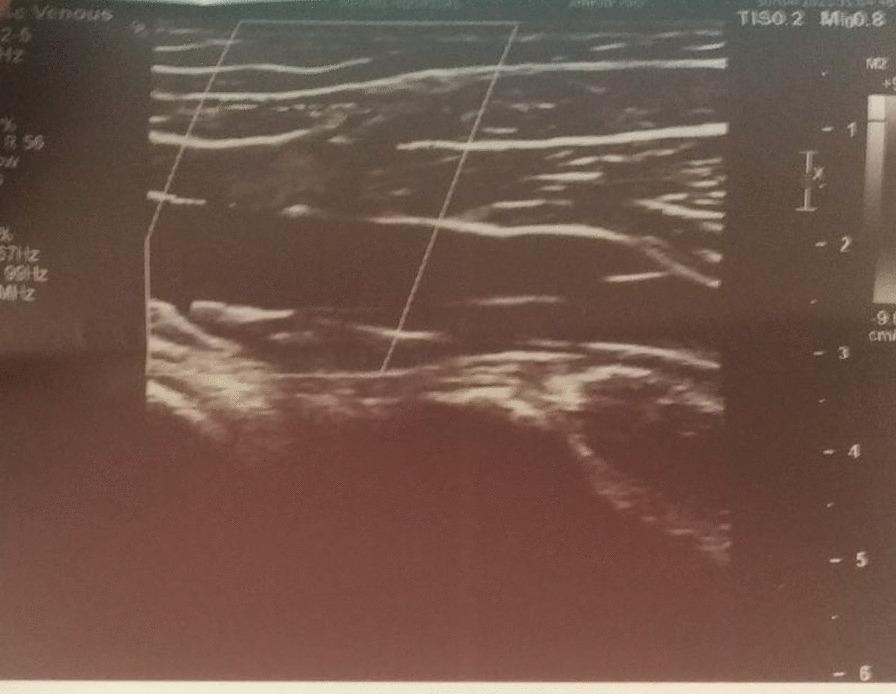

Two cases, a 24-year-old young Chhetri male and a 62-year-old Chhetri female who have received Covishield (ChAdOx1 nCoV-19) vaccine, developed pain in left calf after 2 weeks and 10 weeks of vaccination, respectively. Both the case belongs to the Chhetri ethnic group of Nepal. The pain became severe on the fourth week of immunization in the first case while the pain was acute and severe on the 10 week of vaccination in the second case. The first presented to emergency room and second case was referred to the emergency room from Orthopedic Clinic. On evaluation the first patient had normal vitals with no history of fever and swelling yet displayed non-radiating mild to moderate intensity pain localized to left leg below the knee which became aggravated by movements. In the second case however pain was more intense with other characteristics as first case. Both cases had low wells score (< 4). On local examination tenderness was noted on squeezing but other systemic examination findings of the patient were within normal limits in both cases. Among the numerous vaccines used to fight the battle against COVID-19 disease, the ChAdOx1 nCoV-19 vaccine, Covishield, has been widely used in Nepal and India. Apart from other minor side effects, in few cases thromboses have been reported after vaccination of ChAdOx1 nCoV-19, Covishield, vaccine.

两例患者均为尼泊尔 Chhetri 族裔,一例为 24 岁年轻男性,另一例为 62 岁女性,分别在接种 Covishield(ChAdOx1 nCoV-19)疫苗后 2 周和 10 周出现左小腿疼痛。第一例患者在免疫接种的第 4 周时疼痛加剧,而第二例患者在接种第 10 周时疼痛加剧。第一例患者到急诊室就诊,第二例患者从骨科诊所转至急诊室。评估时,第一例患者生命体征正常,无发热和肿胀病史,但表现为非放射性轻度至中度左小腿以下疼痛,活动时加重。然而,第二例患者的疼痛更为剧烈,且具有与第一例患者相同的其他特征。两例患者的 Wells 评分均较低(<4)。局部检查发现压痛,但两例患者的其他全身检查结果均在正常范围内。在用于对抗 COVID-19 疾病的众多疫苗中,ChAdOx1 nCoV-19 疫苗 Covishield 在尼泊尔和印度得到了广泛应用。除了其他轻微的副作用外,在少数情况下,接种 ChAdOx1 nCoV-19、Covishield 疫苗后也报告了血栓形成。